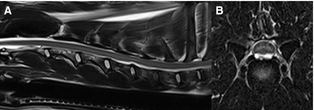

Схоже с этим, но отчетливо различающееся, поражение, описанное в шейном регионе у собак, при котором материал выглядит гиперинтенсивным на T2WMRI сканах, наблюдается вентральнее спинного мозга (Изобр 2). Рентгенологическая интерпретация поддерживает хирургические находки в некоторых случаях, является то, что материал экструдированного гидратированного ядерного материала и может быть ассоциирован с умеренной спинальной компрессией; тяжесть ассоциированной SCI вариабельна.

Изобр 2. T2WMRI изображения от собаки с острым началом неамбулаторнорного тетрапареза и атаксии, локализованной в шейном отделе спинного мозга. (А) Сагиттальные изображения выявили фокальную вентральную экстрадуральную компрессию спинного мозга дорсальнее C5–C6 дискового пространства с ассоциированным сужением дискового пространства и частичной потерей нормального T2 ядерного сигнала.(В) Поперечное изображение через C5/C6 межпозвоночный диск, иллюстрирующее гиперинтенсивный материал вентральнее спинного мозга с изображением типа « чайка».Эти MRI особенности характерны для экструзии гидратированного пульпозного ядра, которая была подтверждена хирургически.